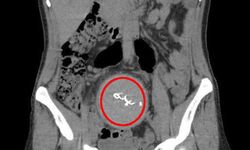

Antalya'da 2021 yılında özel bir hastanede doğum yapan Y.S.'nin (34) vücudunda unutulan 30 santimetrelik gazlı bez, çekilen tomografi ile görüldü....